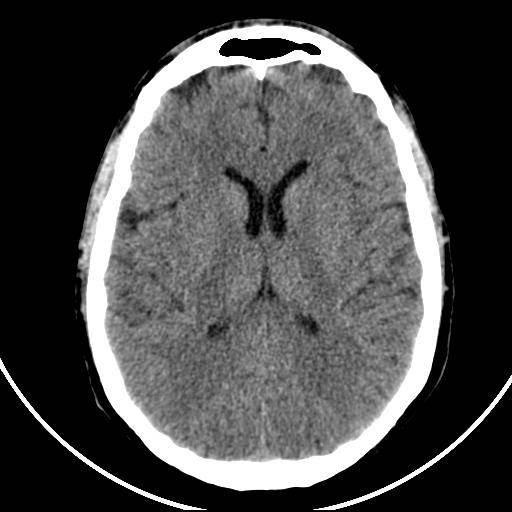

TDM cérébrale